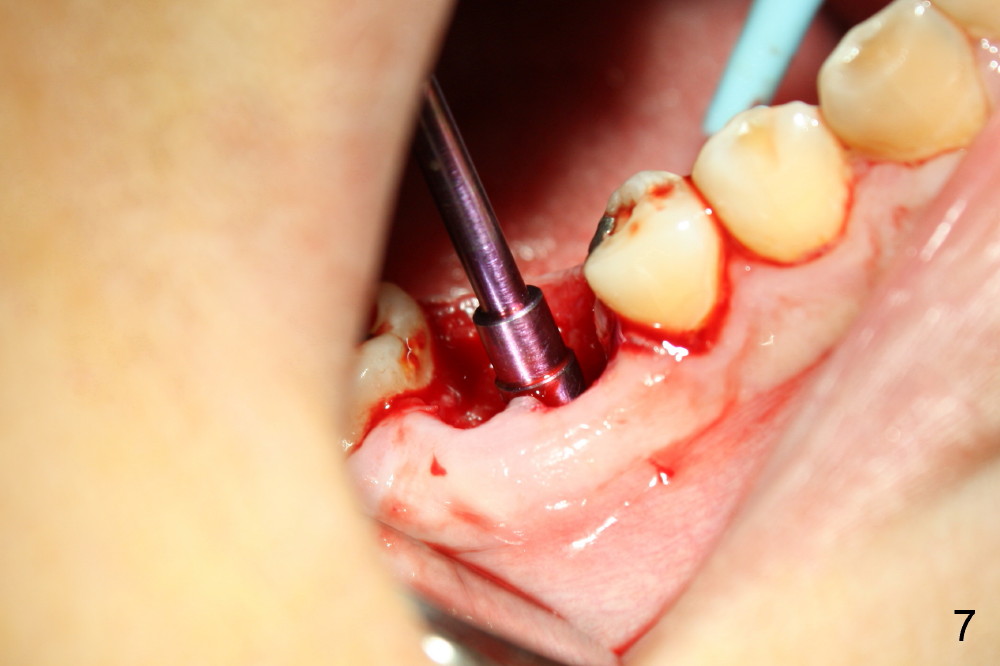

A 38-year-old lady agrees to have implant placement 7 years after loss of the crown of the lower right first molar (Fig.1,2). When the tooth is extracted, the septum is found to be low (Fig.3,4). To confirm it, a PA is taken (Fig.5). To initiate an osteotomy in the septum, it is trans-sectioned with thin osteotomes as shown in Fig.4 insert (black line). A 2 mm pilot drill is placed in the septum (Fig.6: P). The osteotomy is enlarged by 2.5-4.0 mm reamers (Fig.7,8), followed by insertion of 6x17 mm tapered tap at the depth 14 mm (Fig.9). The osteotomy is further enlarged by 4.5 and 5.0 mm reamers. A 6.0x14 mm one piece implant is placed initially. The trajectory is not ideal. A 6.0x14 mm one piece implant is placed initially. The trajectory is not ideal. The implant is removed from the osteotomy partially and reinserted with improved trajectory (Fig.11, compare to Fig.10 (red line)). Primary stability is high. There is not much bone mesiodistally so that the trajectory is easily changed in that direction. After abutment preparation, mixture of autogenous bone (harvested from reamers) and allograft is placed in the residual mesial and distal sockets (Fig.12). To contain the bone graft, an immediate provisional is placed (Fig.13 P). The occlusal plane of the provisional is significantly lower than that of the adjacent teeth to avoid micromovement of the implant. The patient is advised to eat soft food on the left side. Six days postop, the patient returns for prophy. The provisional is removed; the bone graft appears to be incorporating into the socket (Fig.14). After recementation, the provisional remains in place for 3.5 months; PA shows increased bone density in the mesial and distal sockets (Fig.15, compare to Fig.5,11). Due to insurance coverage, the patient defers fabrication of definitive restoration for at least 7 months. The immediate provisional is finally lost 8.5 months postop: the gingiva attaches to the 1-piece implant (Fig.16), while the density of the mesial socket increases (Fig.17 *) with formation of the cortex (lamina dura) coronally (v). Before the provisional (Fig.18 P) is removed for cementation of the definitive restoration, black shadow (*) is noted over the buccal gingiva. It is partially due to buccal placement (Fig.19) and partially due to buccal atrophy over a period of 10.5 months postop. How to prevent buccal placement? Positioning the first pilot drill in the septum buccolingually is a key. Eleven months post crown (Fig.20 C) cementation, the black shadow remains, but there is no tenderness. If the implant threads are immediately underneath the periosteum, there is tenderness.